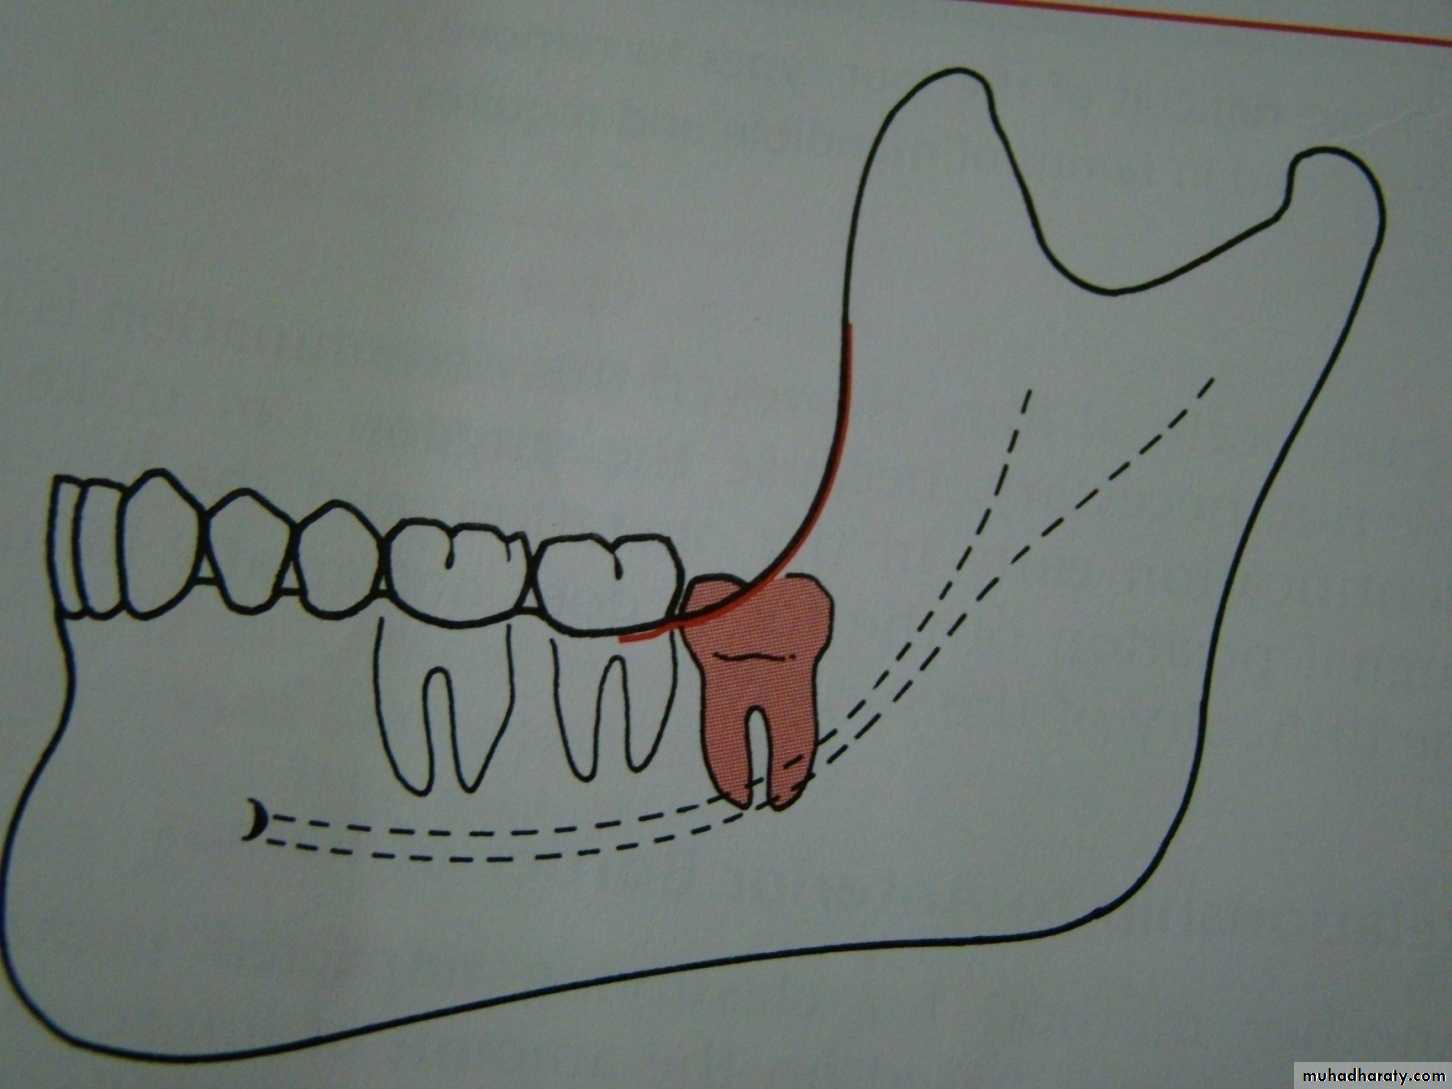

Winters classification of impacted lower third molar

Mesio angularDisto angular

Horizontal

Vertical

Inverted

Transverse

Buccoversion

Linguversion